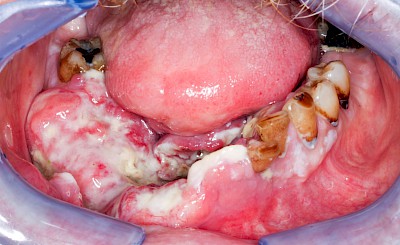

Schwellung ohne Eiter: faltenförmig

Als Sonderform des Reizfibroms können bei Zahnprothesen in den Randbereichen selten am Gaumen, häufiger außen in den Umschlagfalten in Ober- und Unterkiefer auch lappenartige Auffaltungen (Lappenfibrome) beobachtet werden, die ebenfalls aufgrund eines mechanischen Dauerreizes entstehen. Alle diese Veränderungen sind in der Regel eher wenig schmerzhaft – auch wenn man darauf drückt. Hier sollte zeitnah mit einem Zahnarzt eine Abklärung erfolgen.